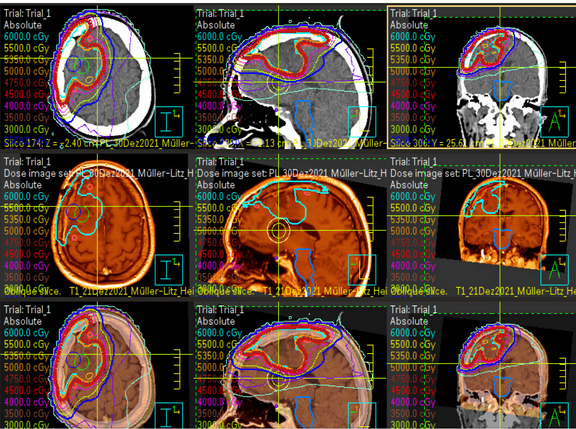

Strahlentherapie ist eine weitere Methode, um Hirntumore zu behandeln. Sie zielt darauf ab, Krebszellen präzise zu zerstören, ohne das umliegende gesunde Gewebe zu beschädigen. Die Klinik für Strahlentherapie führt die Strahlentherapie durch. Unser Team wird Sie dabei mit unterstützen und informieren, um den Prozess so angenehm wie möglich zu gestalten.